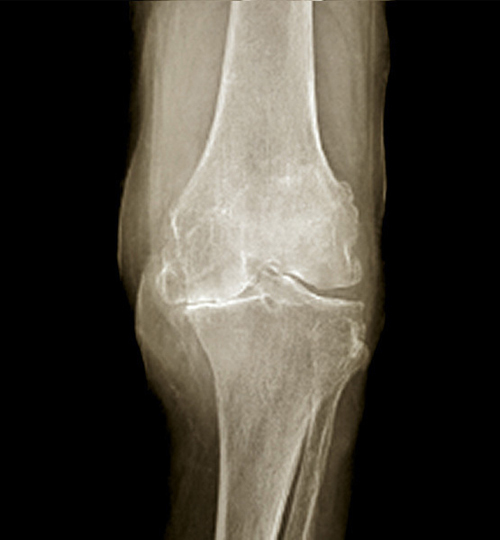

Les participants (N = 155) étaient âgés en moyenne de 61 ans et 64 % étaient des femmes. Ils avaient un diagnostic de gonarthrose primaire sévère (grades 3 à 4 sur l’échelle Kellgren-Lawrence), avec une douleur modérée à sévère présente la plupart des jours sur les 3 mois précédents (≥ 4/10 sur une échelle numérique) répondant insuffisamment à l’antalgie usuelle. Les critères d’exclusion comprenaient : la présence d’une arthrite inflammatoire ou d’une fibromyalgie, l’utilisation d’injections intra-articulaire d’acide hyaluronique au cours des 4 mois précédents ou d’une corticothérapie au cours des 3 mois précédents.